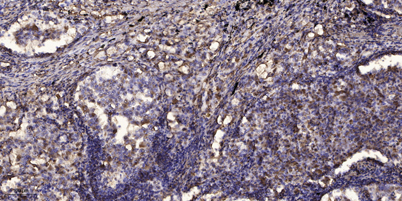

Applications IHC

Recomended Dilution IHC-p 1:50-300